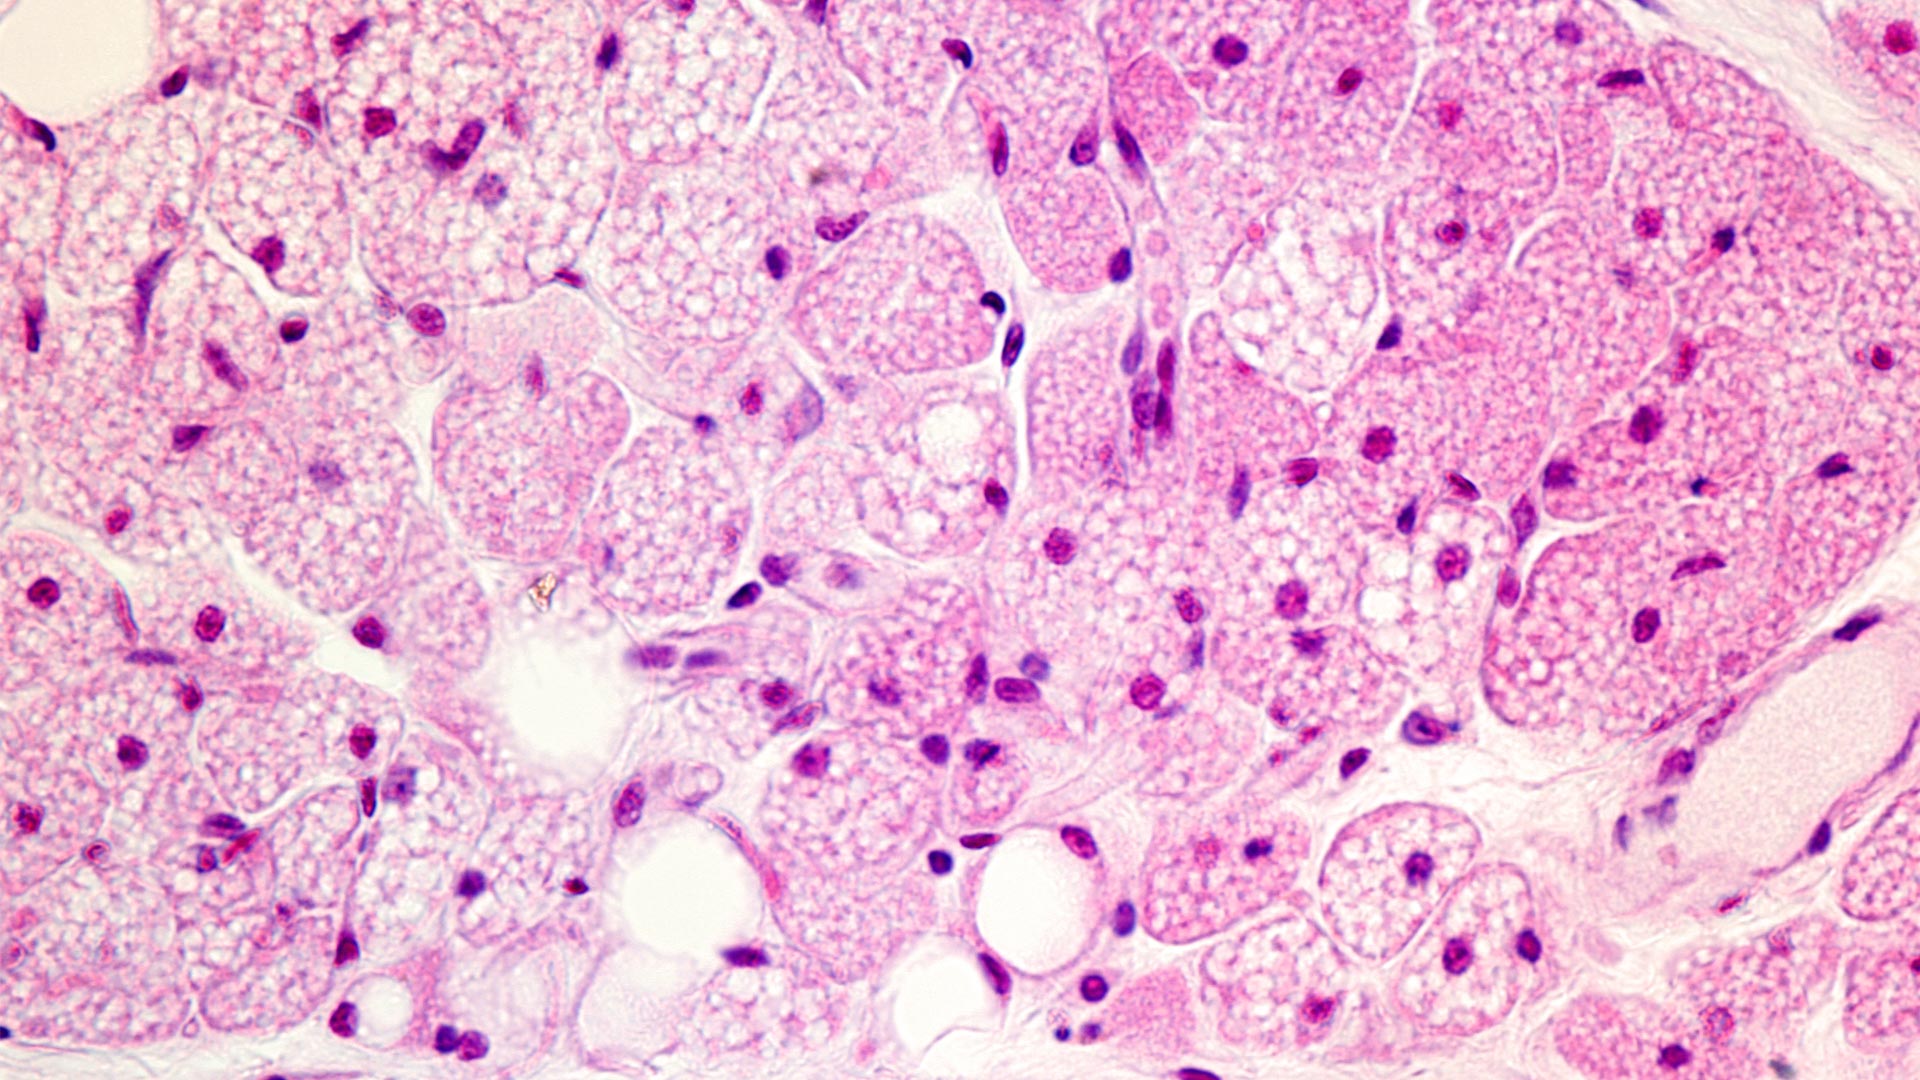

One major laboratory project is the investigation of adipocyte progenitor cells, adipocyte programmed cell death and adipose tissue fibrosis that is induced by high fat feeding. In these studies, we have utilized a variety of experimental approaches including genetically engineered mice, Fluorescent Activated Cell Sorting (FACS) analyses and sorting along RNA-Seq and single nuclei RNA-Seq. In these analyses we isolated a variety of inflammatory specific cell types within adipose tissue and have taken extensive use of RNAseq technology to characterize the expression profiles of these various cell subsets. This approach has allowed us to develop a functional understanding of the signaling interplay between the adipose tissue immune cell types to determine the specific role each cell is playing in the inflammatory response. In collaboration with the laboratory of Kosaku Shinoda we are exploring the relationship between metabolism, autophagy and energy balance in adipocyte lineage determination (brown, beige and white) as a potential therapeutic approach for both diabetes and obesity.

A second major laboratory project is based upon our recent findings in collaboration with the laboratory of Fajun Yang that in the fed state CDK8/CycC complex directly phosphorylates the nuclear form of SREBP-1c that induces an E3 ligase mediated ubiquitination and proteasome-mediated degradation of SREBP-1c. This process is one of several that is required to maintain nuclear SREBP1-c at very low levels thereby suppresses lipogenic gene expression and lipogenesis. However, n the fed state, CDK8/CycC proteins are rapidly down regulated through a mTORC1 dependent pathway leading to increased SREBP-1c stability and increased lipogenic gene expression and lipogenesis. During the past two years, we have developed a robust research team, several key mouse genetic models, human liver biopsy speciments and cell based approaches to investigate the regulation of liver gluconeogenesis abd lipogenesis in normal and pathophysiologic states of insulin resistance, obesity and non-alcoholic fatty liver disease (NFALD). In these approaches we perform various high-through put DNA sequencing technologies (ie: RNA-seq, single cell RNA-seq, ChIP-seq, 3 dimensional DNA conformation capture (Hi-C) that are used to directly assess the epigenetic basis of normal and pathological liver metabolic funciton.